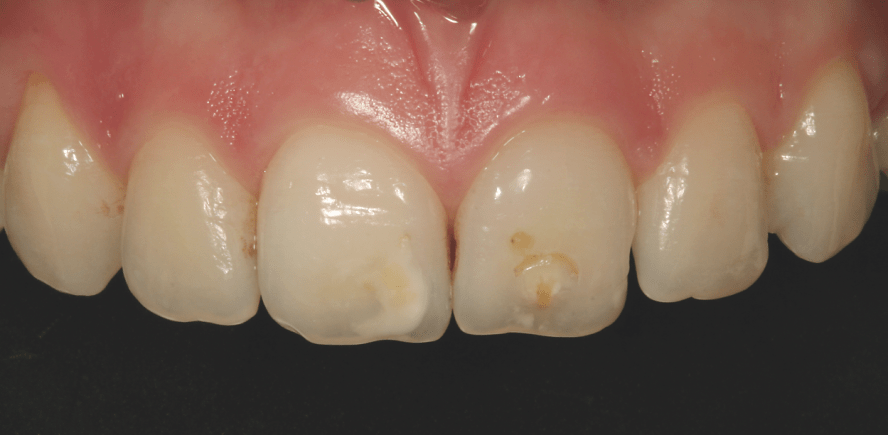

Klinischer Anwenderbericht

Neben den immer besseren chemisch-physikalischen Eigenschaften zeichnen sich State of the Art-Komposite heute auch durch einfach zu verstehende Farbsysteme aus. Beim vorliegenden Komposit (Venus Diamond Heraeus) können die Kompositmassen grundsätzlich in drei Gruppen eingeteilt werden:

Daneben stehen als vierte Gruppe Effektmassen zur Verfügung, z.B. die Bleachfarben BL und BXL sowie opaleszierende Massen YO und CO. In den allermeisten klinischen Situationen können bereits mit zwei bis drei Massen pro Restauration sehr naturnahe Resultate erreicht werden. Geschichtet wird nach der klassischen Technik, wie von Hotz und Magne 1996 beschrieben.12 Die Massen sind sehr kompakt mit einer herausragenden festen Konsistenz. Sie lassen sich zügig verarbeiten, ohne am Instrument zu kleben. Einmal modellierte Konturen bleiben perfekt stehen und zerfliessen nicht. Die Politur erfolgt mit dem eigens auf Hybridkomposit abgestimmten Venus Supra Poliersystem von Heraeus. In wenigen Schritten lässt sich so komfortabel eine gefällige Oberflächenqualität erreichen. Die hohe Röntgenopazität macht die radiologische Beurteilung der erstellten Restaurationen einfach und sicher.

Die modernen Kompositsysteme sind für sämtliche Indikationen von Klasse I–V-Kavitäten sowie für indirekte Restaurationen geeignet. Mit ihren hochentwickelten mechanischen und optischen Eigenschaften stellen sie eine echte Alternative zu klassischen Techniken wie metallischen und keramischen Restaurationen dar. Die Qualität der Resultate und der Anspruch zur universellen Anwendung legt eine neue semantische Klassifikation für nanooptimierte Mikrohybridkompositsysteme nahe: die plastische Dentalkeramik.